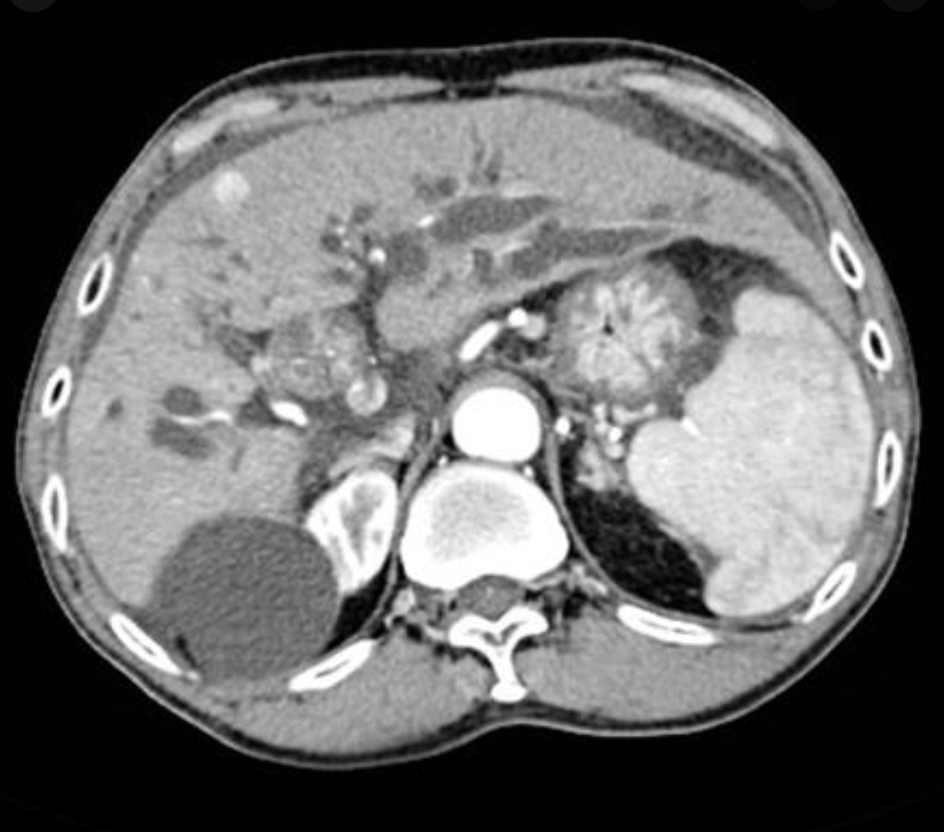

Px: bug involved; what does this lead to?

Ex: where?

Ix: triad.

Sequela-1

Dx: type 4A choledochal cyst.